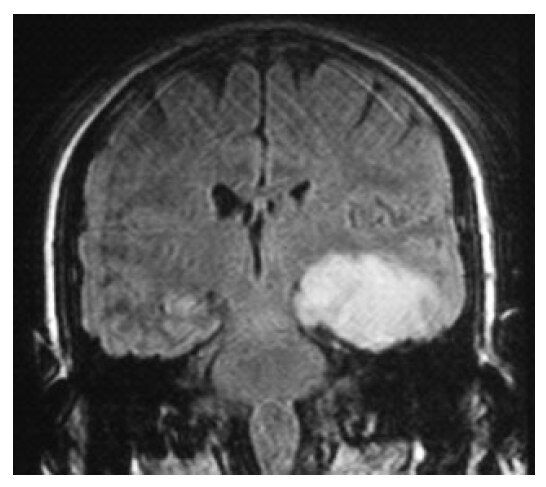

С этим МРТ

Срез прошел через островковую кору и мы видим указанный отек

Здесь кровоизлияние есть

А здесь что? Похож на вчг